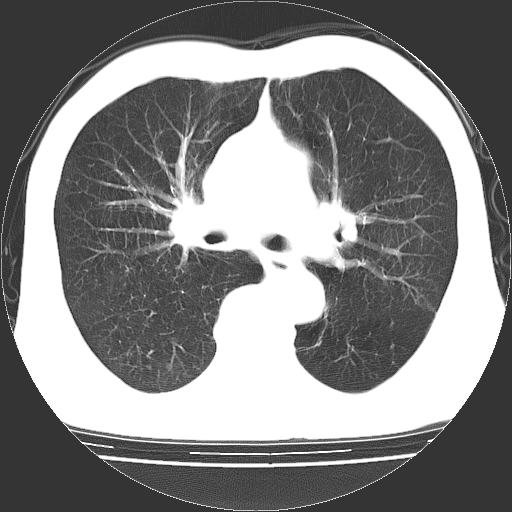

以下是引用hhcckk在2009-1-1 15:38:00的发言:[br]左下肺少许絮状模糊影--考虑感染[br]两肺散在小点状密度增高影--结合病史考虑矽肺?[br]气管壁钙化--可能由于老年退变性引起的